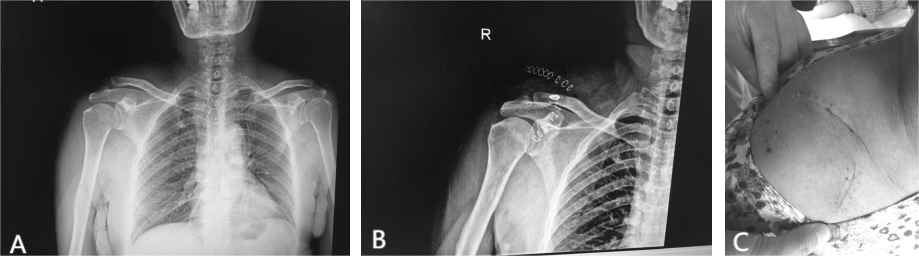

После успешной анестезии посредством блокады плечевого сплетения пациента укладывают на спину с приподнятым пораженным плечом, регулярно дезинфицируют и накладывают драпировку. Делают разрез на внешней стороне ключицы пораженной стороны, кожу, подкожную клетчатку, и глубокую фасцию разрезают, чтобы обнажить пораженное плечо. В ходе операции установлено, что акромиально-ключичный сустав вывихнут, латеральный конец ключицы смещен вперед и вверх, имеется разрыв акромиально-ключичной и клювовидно-ключичной связок. Удалить гематому, просверлить отверстия на дорсальной стороне на расстоянии 2 см и 4 см от дистального конца ключицы, установить на дорсальной стороне 2 фиксирующие петлевые стальные пластины и с помощью высокопрочных спиц обойти основание клювовидного отростка для возврата в исходное положение. акромиально-ключичного сустава и временно фиксируют его спицами Киршнера.При удовлетворительном вправлении акромиально-ключичного сустава высокопрочную нить на фиксирующей петле стальной пластины затягивают и завязывают, спицу Киршнера удаляют, акромиально-ключичный сустав ремонтируют, рану промывают физиологическим раствором и послойно зашивали (рис. 2).

Рисунок 2. А — рентгенограмма пораженного плеча до операции, Б — рентгенограмма пораженного плеча после операции, С — послеоперационная рана.